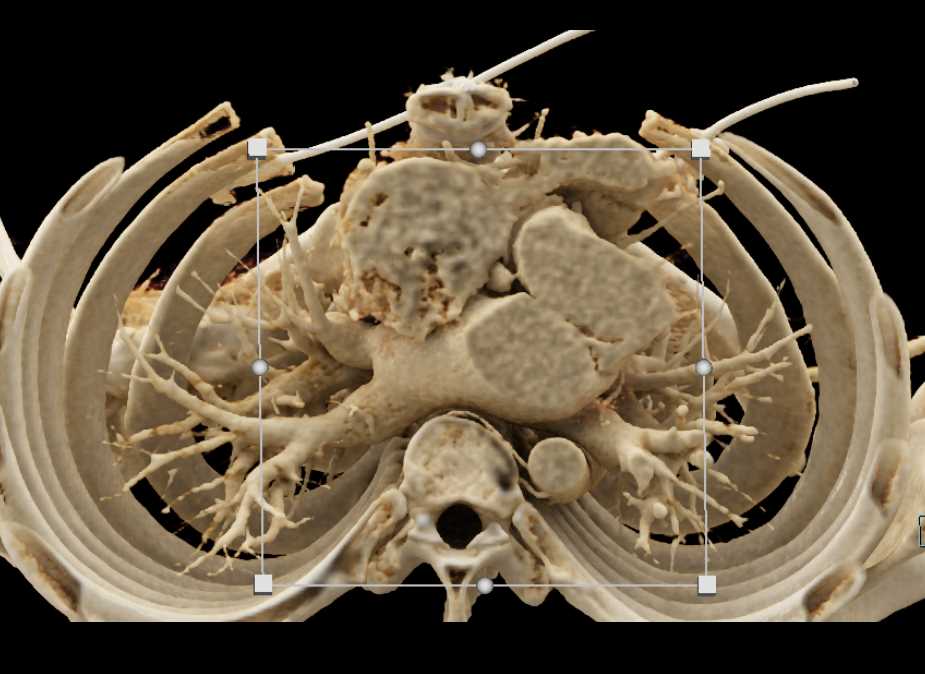

Aortic Valve Repair